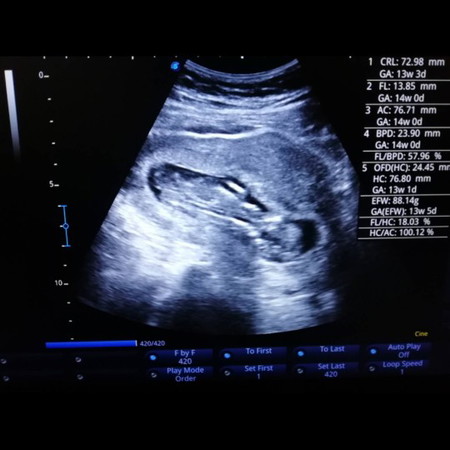

13w3d นน 88g หมอหาจู๋ไม่เจอค่ะ

16-20w อัพค่ะคุณแม่ 13w ยังเล็กไปที่จะดูเพศนะคะ นอกจากตรวจ nifty ค่ะ บ้านนี้รู้ก่อน 12w เพราะผลตรวจ nifty ค่ะ